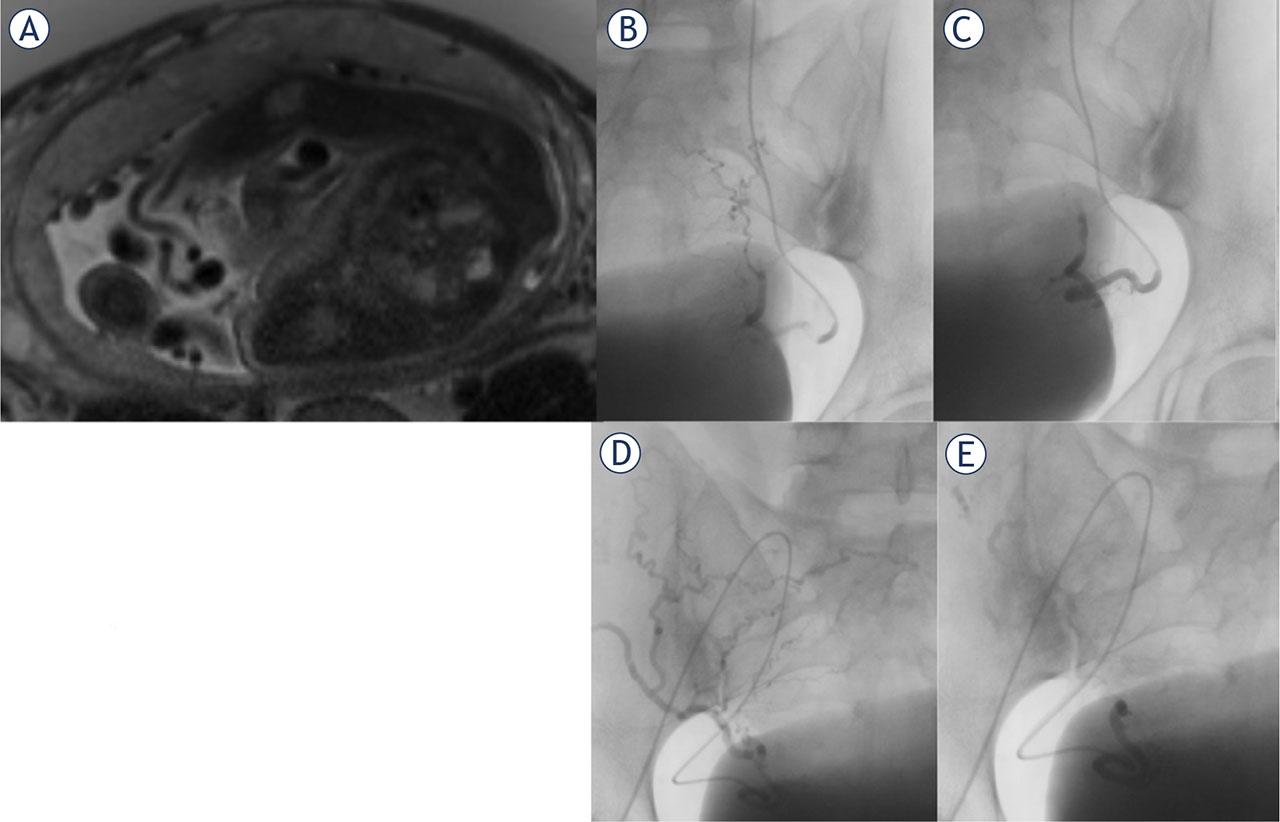

Figure 2.